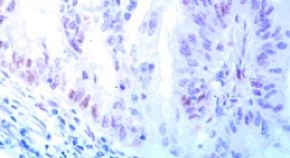

This article considers the case of a 58-year-old man who presented with a 35-year history of Crohn's disease, pararectal fistulas and abscess formation. He had been taking azathioprine therapy for approximately 5.5 years. He was started on infliximab; however, his fistulas persisted and the abscess recurred. He was, therefore, switched to adalimumab. After development of pancytopenia, a bone marrow biopsy and a diagnostic splenectomy were performed, leading to a diagnosis of hepatosplenic T-cell lymphoma.